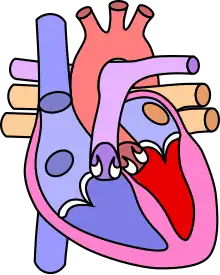

Diagram of a healthy heart and one with tetralogy of Fallot

"Tetralogy" denotes four parts, here implying the syndrome's four anatomic defects.[2] This is not to be confused with the similarly named teratology, a field of medicine concerned with abnormal development and congenital malformations (including tetralogy of Fallot). Below are the four heart malformations that present together in tetralogy of Fallot:

Heart with tetralogy of fallot A: Pulmonary stenosis; B: Overriding aorta; C: Ventricular septal defect (VSD); D: Right ventricular hypertrophy

Normal heart